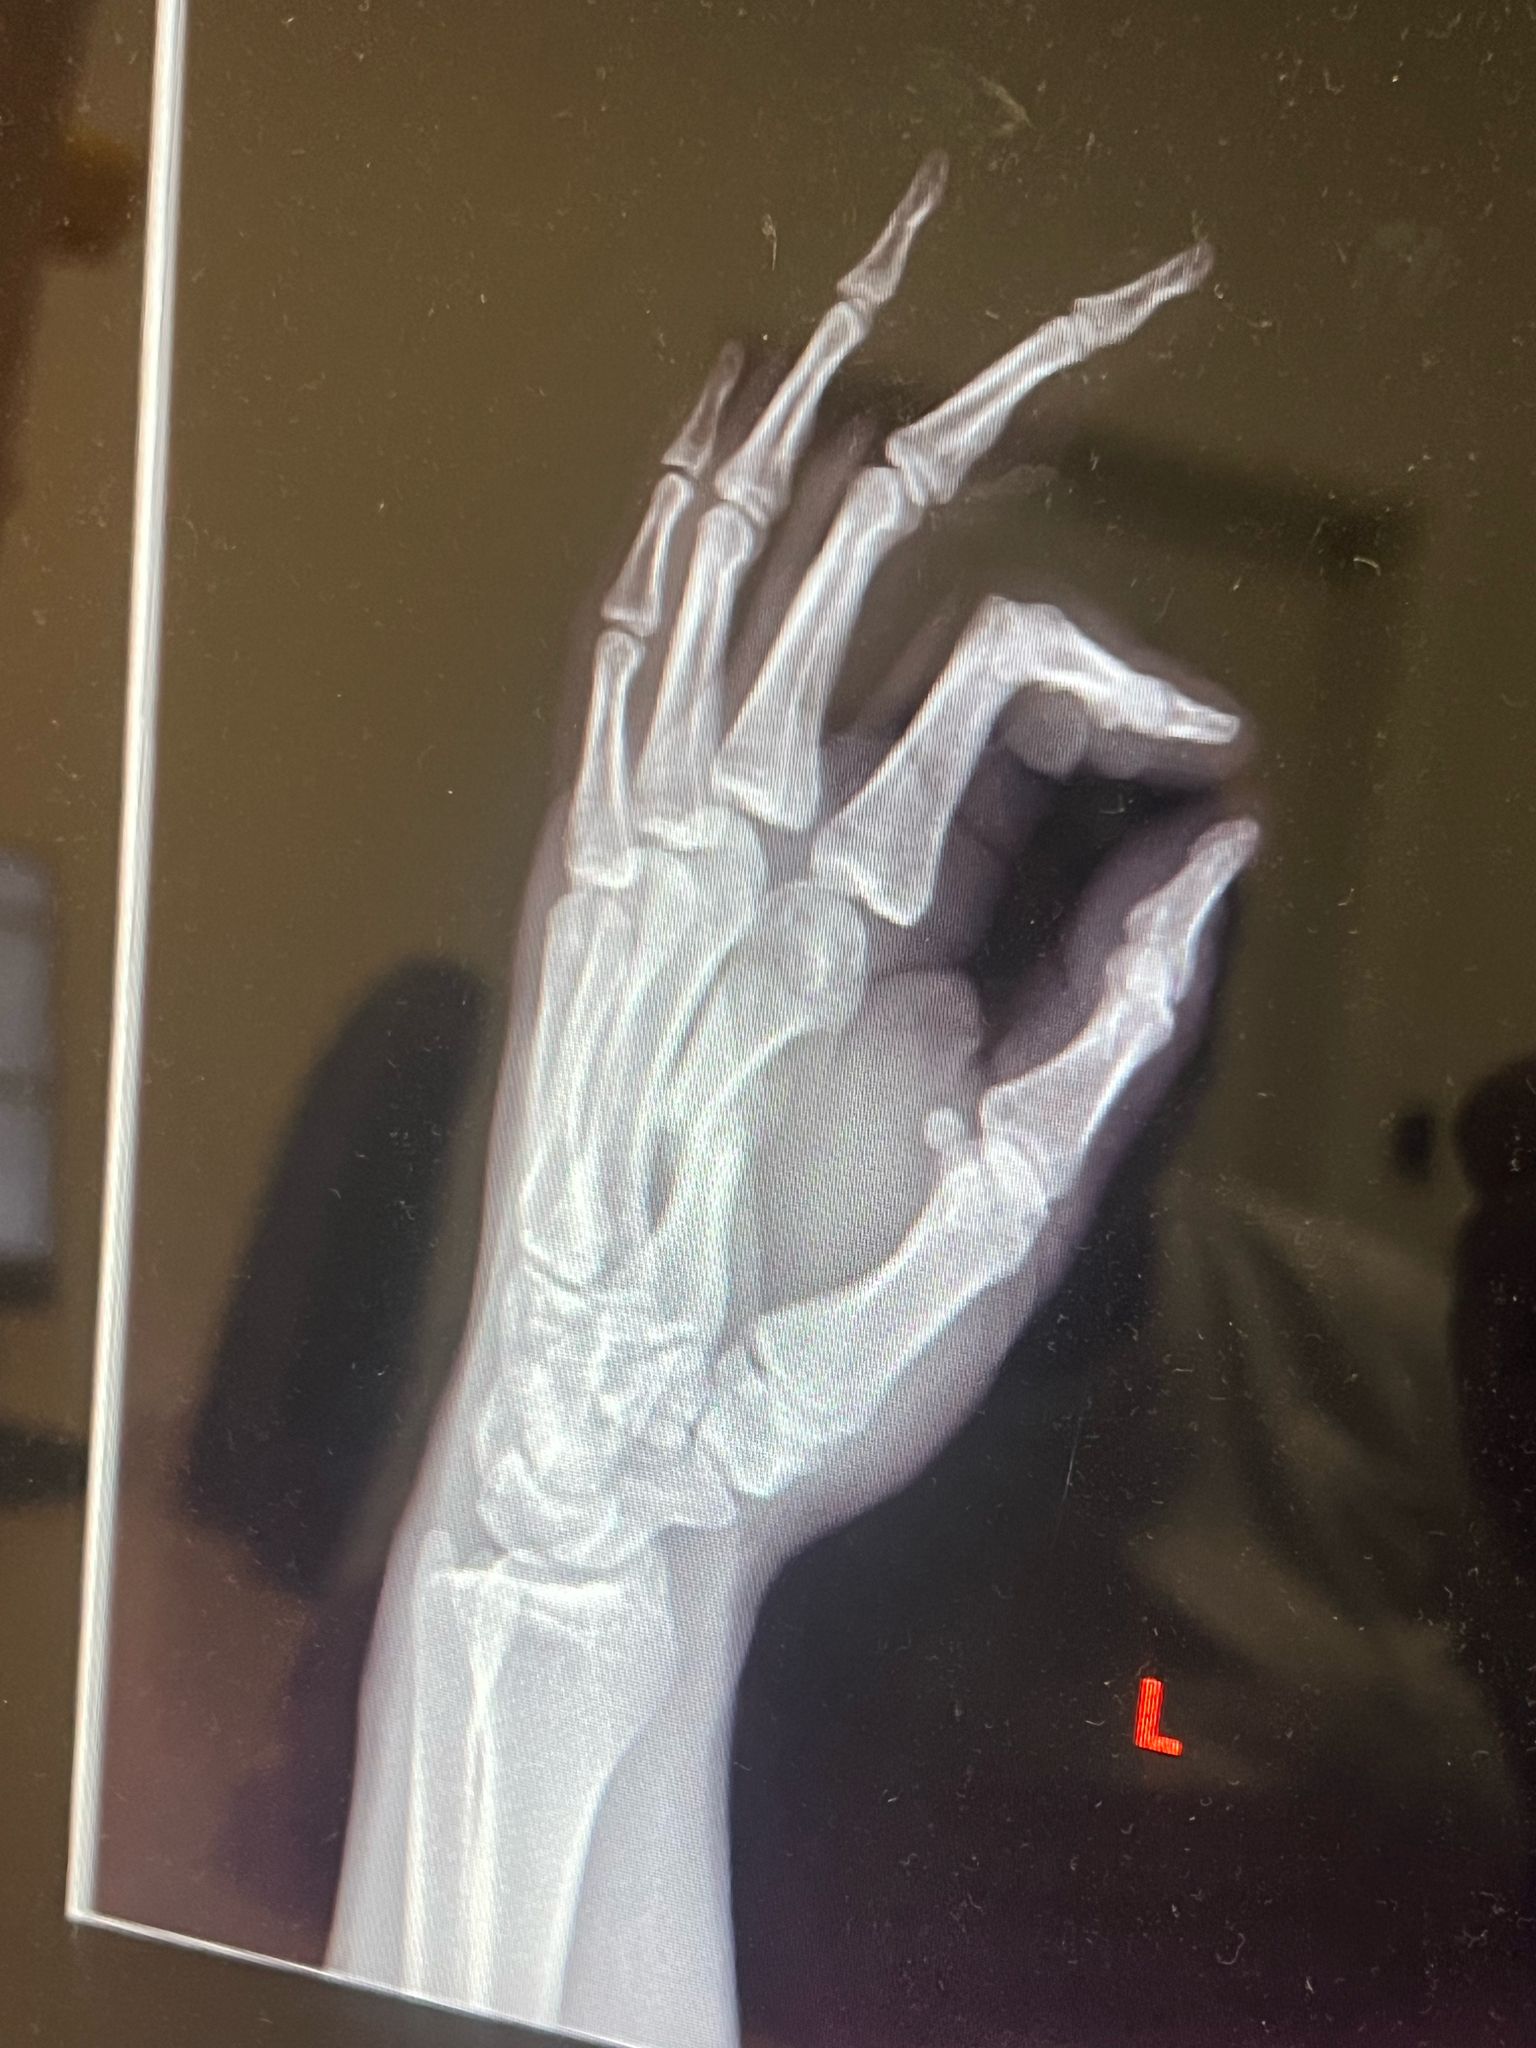

• Zranenie: 4. 6. 2024 – zlomená zaprstná kosť

• Operácia (osteotómia): 27. 10. 2024

Osteotómia je chirurgický zákrok, pri ktorom sa kosť prerezáva a presne nastaví tak, aby mohla správne zrast. Po takejto operácii predstavuje hlavnú výzvu najmä kvalita zhojeného kostného tkaniva, opuch, bolesť a obmedzenie pohyblivosti. Práve terapia LIMFA tu zohrala kľúčovú úlohu.